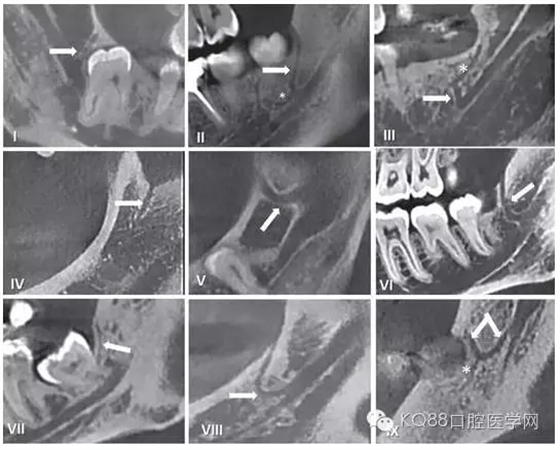

在臨床工作中,個(gè)體解剖差異導(dǎo)致像磨牙后管這類的神經(jīng)分叉及神經(jīng)走行的變化,術(shù)前只能通過放射方法檢測(cè)。但使用口腔曲面斷層片之類的常規(guī)二維影像學(xué)照片是難以檢查到的。隨著現(xiàn)代醫(yī)學(xué)影像技術(shù)的發(fā)展,出現(xiàn)了計(jì)算機(jī)斷層掃描(CT)和錐束CT(CBCT),其在口腔醫(yī)學(xué)領(lǐng)域的成功運(yùn)用使得磨牙后管的術(shù)前影像評(píng)估成為可能。精確的捕捉到下頜磨牙后管的解剖走行,需要高分辨率的成像設(shè)備并保證攝像期間患者沒有晃動(dòng)。下面我們將用幾張CBCT影像圖片為大家圖示說明。

圖五 使用CBCT拍攝到的不同走行的下頜后管

通過對(duì)磨牙后三角(RMT),磨牙后孔(RMF)和磨牙后管(RMC)解剖學(xué)結(jié)構(gòu)及其臨床走行的認(rèn)識(shí),將會(huì)幫助我們?cè)谂R床工作中,進(jìn)一步減少磨牙后區(qū)操作所造成的意外損傷。